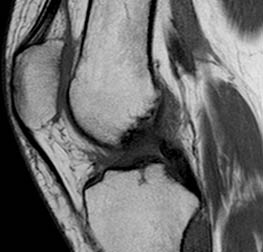

Il ginocchio, insieme alla spalla e la caviglia, è tra le articolazioni più esaminate in Risonanza Magnetica (RM) a causa dell’elevata incidenza di patologie o dolori: è estremamente mobile, spesso sollecitato durante l’attività fisica ed è responsabile della stabilità del corpo durante il carico. Anche se questro distretto è spesso affetto da dolori cronici, le lesioni traumatiche si verificano con elevata frequenza soprattutto nei soggetti giovani. Lesioni ossee possono coesistere con quelle legamentose, tendinee o cartilaginee mentre più rare le lesioni muscolari. La risonanza magnetica è estremamente diagnostica nelle patologie del ginocchio e permette di analizzare nel dettaglio i menischi, i legamenti i tendini e con particolari sequenze anche le cartilagini, non solo in modo visivo (analisi diretta sulle immagini) ma anche con la quantificazione del contenuto di acqua nei differenti tessuti utile a determinare la possibile esistenza di iniziali fenomeni degenerativi.